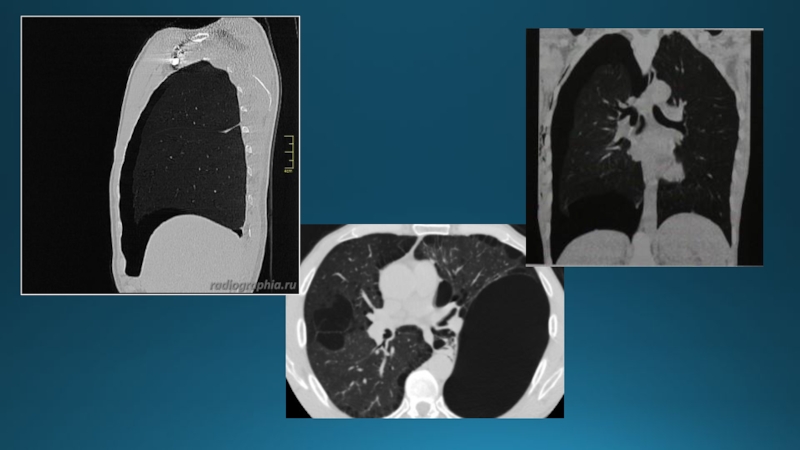

Слайд 8Компьютерлі томография

Компьютерлі томография